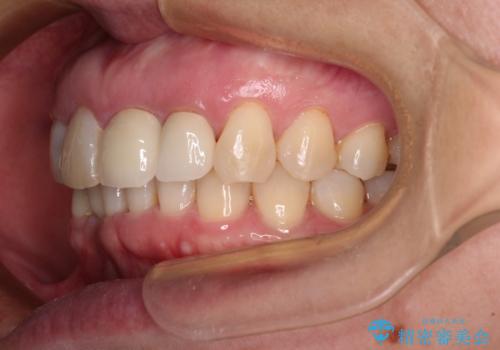

- 下顎前歯が抜けそうとのことで来院された患者様です。

初診の状態ではすぐにでも抜けそうな状態で、インプラントによる補綴治療を行うこととしました。

インプラント治療に際し、前歯の叢生に対する矯正治療を提案したところ、興味を持たれたので、インビザライン・ライトによる矯正治療を行うこととしました。

抜歯後にスペースができると恥ずかしいため、抜歯した歯を接着剤で固定した上で矯正治療を行い、その後インプラントやオールセラミッククラウンの装着を行うこととしました。